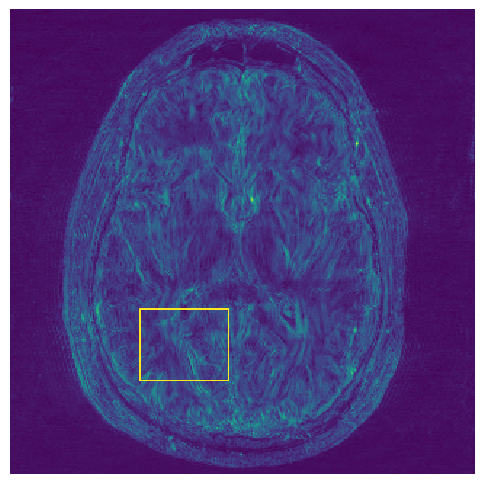

5.2 Uncertainty Assessment

We calculated the mean value of the std. maps, obtained by our method and the Monte Carlo Dropout method, for all images in the inference set and utilized it as an uncertainty measure. The correlation between these uncertainty measures and reconstruction error (MSE) is depicted in Fig. 4. Our NPB-REC uncertainty measure exhibits a higher correlation with the Reconstruction error compared to Dropout (Pearson correlation coefficient of r=0.93𝑟0.93r=0.93 vs. r=0.89𝑟0.89r=0.89). Further, fig. 4LABEL:sub@fig3:c demonstrates our uncertainty measures correlate better with the acceleration rates used during acquisition. These outcomes, in turn, indicate the ability of our uncertainty measure to detect unreliable reconstruction performance. It is worth mentioning that the strong linearity of the correlation exhibited was preserved even for higher acceleration rates and when we repeated the same experiments on the knee test set (in all cases we obtained r>0.92𝑟0.92r>0.92).

Fig. 5 presents the uncertainty values measured in the cases of anatomical and undersampling mask distribution shifts. For the anatomical distribution shift, we considered the following scenarios: brain test set when the predictive model is trained on brain images as well (B-B), the same model tested on knee data (K-B), training and testing the model on the knee dataset (K-K) and the same model tested on brain data (B-K). Our uncertainty measures were significantly higher for the out-of-distribution cases compared to the within-distribution cases for both anatomical and undersampling mask distributions. In contrast, the uncertainty measures of Dropout method don’t show a significant difference in the case of anatomical shifts from knee to brain (see top-right part in Fig. 5).